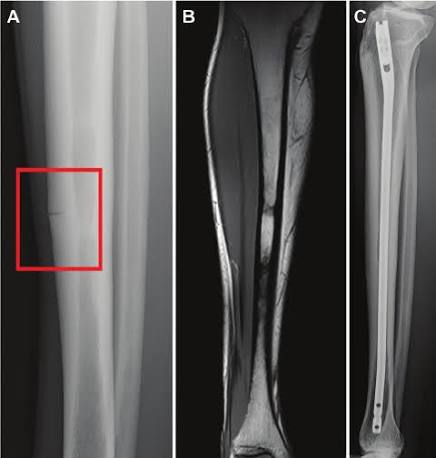

| Example imaging, not from this athlete, showing the classic “dreaded black line” in the anterior tibia. Sources: Fredericson MRI Grading System for Tibial Stress Injuries Fredericson M, Bergman AG, Hoffman KL, Dillingham MS. Tibial stress reaction in runners: correlation of clinical symptoms and scintigraphy with a new magnetic resonance imaging grading system. International Journal of Sports Medicine. 1995;16(6):452–456. Reaffirmed in: Warden SJ et al. Stress fracture injury classification and grading system using MRI. Journal of Orthopaedic & Sports Physical Therapy. 2019;49(9):653–663. High- vs Low-Risk Bone-Stress Injury Site Classification Arendt EA, et al. Consensus statement on classification, diagnosis and management of bone stress injuries: a modified Delphi approach. British Journal of Sports Medicine. 2021;55(20):1106–1115. Consensus Guidelines for Management and Return-to-Sport Progression Nattiv A, et al. Stress fracture consensus statement. British Journal of Sports Medicine. 2013;47(9):469–475. Warden SJ, et al. Stress fractures: pathophysiology, epidemiology, and risk factors. Clinics in Sports Medicine. 2019;38(4):481–494. |